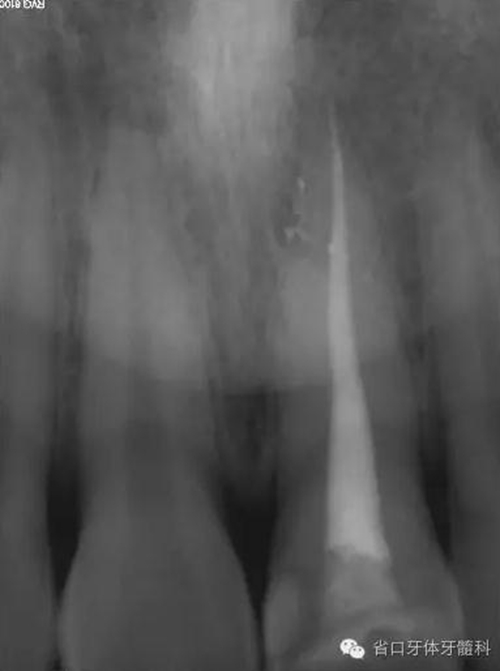

術(shù)前X線片

X線片示21冠折,根段未見明顯牙折影像。